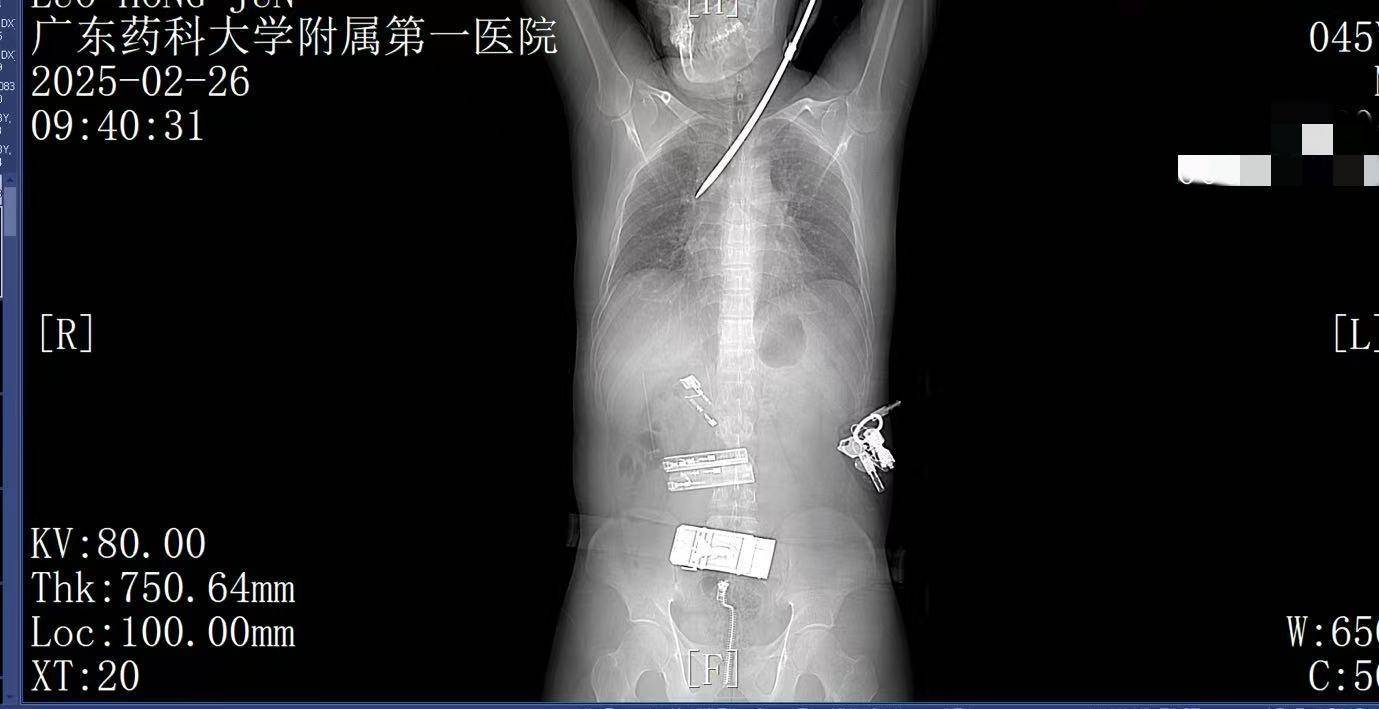

9:39,救护车到达医院大门,院内急救团队已经做好准备实盘虚拟币。在紧密监护的情况下,全程采用绿色通道。到达医院时,罗师傅已经面色苍白,呼吸急促。螺丝刀已深深刺入罗师傅右肺,随时可能因大出血而危及生命。

9:41,快速完成头+胸+腹部CT检查,经多学科会诊,明确螺丝刀异物刺入肺部实盘虚拟币。CT显示螺丝刀紧贴肋间血管、上肺后段动脉,尖端距右肺门仅2厘米,一旦贸然拔出螺丝刀,极有可能引发大出血,导致失血性休克甚至死亡,必须紧急手术。